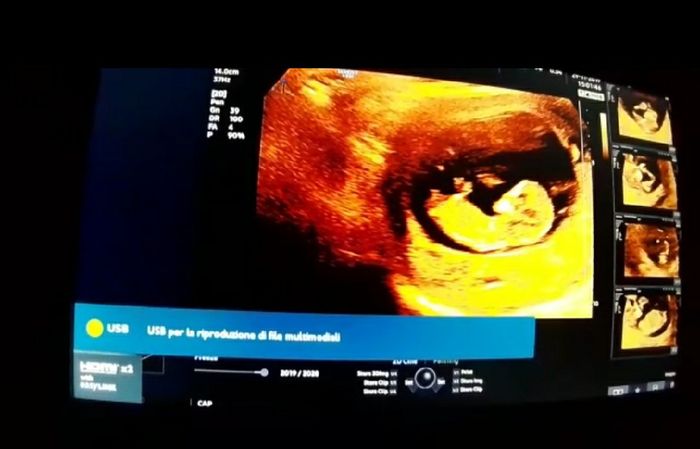

Oggi ho fatto la traslucenza ma il ginecologo non ha saputo dirmi nulla sul sesso..ho fatto qualche screen dal video che ha girato mio marito..secondo voi si può capire qualcosa? A me sembra di vedere il tubercolo ma non capisco...